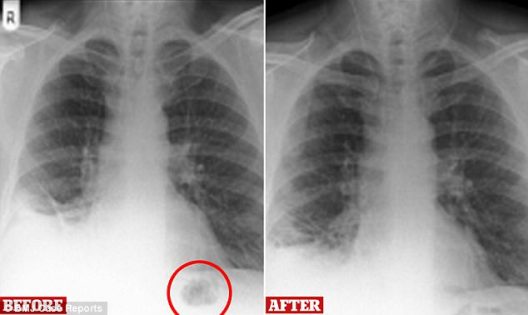

منوعات / الكوثر: شخص الأطباء حالة رجل بريطاني بأنه مصاب بمرض سرطان بعد أن وجدوا كتلة في رئتيه، ولكن ما تم اكتشافه لاحقاً كان غريباً وصادماً.

وأظهرت الفحوص كتلة في رئتيه والتي افترضها الخبراء الاستشاريون أنها علامة على السرطان بسبب تدخينه لمدة 3 عقود وأحالوه على وجه السرعة إلى المستشفى وفقًا لصحيفة “ديلي ميل” البريطانية.

وخلال إجراء فحص لمجرى الهواء اكتشف الأطباء أن الكتلة هي مخروط من مجموعة “بلايموبيل” وهي لعبة التي ابتلعها الرجل منذ 40 عامًا.

وتم تنفيذ تنظير القصبات في مستشفى “رويال بريستون” بعد إحالة المريض بسبب المخاوف بوجود علامة على الإصابة بالسرطان، بعد فترة وجيزة من إجراء هذا التنظير، كشف المريض أنه كان يلعب بانتظام وبلع قطعة من “بلايموبيل”.